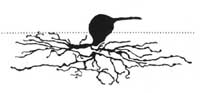

Kdybychom tak uměli spočítat množství gangliových buněk jako umíme změřit nitrooční tlak! To by se nám diagnostikoval glaukom! Na množství gangliových buněk můžeme jen usuzovat podle svazečků nervových vláken na sítnici a podle šíře neuroretinálního lemu terče zrakového nervu. Sledování změn vrstvy nervových vláken je citlivější pro včasné poznání glaukomu než sledování terče samotného. Vzhledem k variabilitě terče je obtížné stanovit jednotnou normu pro všechny lidi. Vrstva nervových vláken morfologicky je však téměř stejná u každého člověka!

Nervová vlákna

Jsme schopni sledovat vrstvu nervových vláken v každodenní praxi bez nákladných přístrojů? Ano!

Vyšetření vrstvy nervových vláken indirektní biomikroskopií

- štěrbinová lampa s paprskem rovnoběžným s osou našeho pohledu

- 60-90 D čočka nebo čočka Goldmanova

- Pacient v mydriáze

Na snímku vidíme nastavení ramene štěrbinové lampy rovnoběžně s osou našeho pohledu. Pacient se dívá druhým okem 15 stupňů směrem temporálně.

Modrá šipka - ukazuje plochu na sítnici, která obsahuje nervová vlákna. Sítnice je jemně proužkovaná, světlejší, cévy "jsou jako pod závojem". Červená šipka - ukazuje místo bez nervových vláken. Sítnice je tmavší, bez proužkování. Cévy jsou ohraničeny neobvykle ostře.